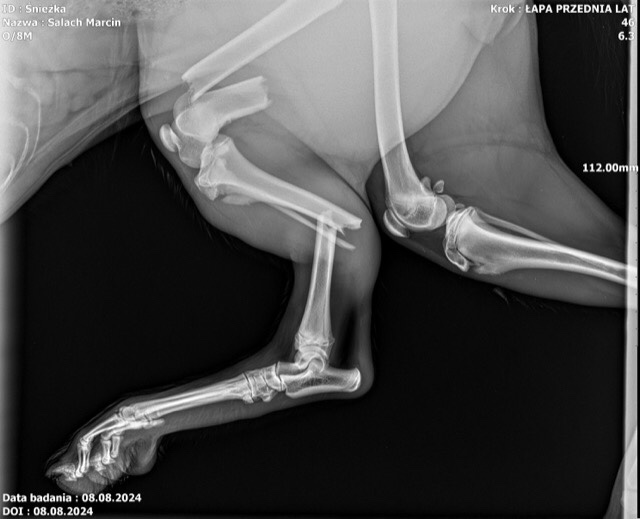

Dostałem ją od kolegi który jest hodowcą, za darmo, ponieważ została mu ostatnia z miotu i nikogo nie zainteresowała bo ludzie z reguły wolą samce,.Nie stać mnie na operacje łapy. W lewej tylnej ma złamane aż trzy kości.